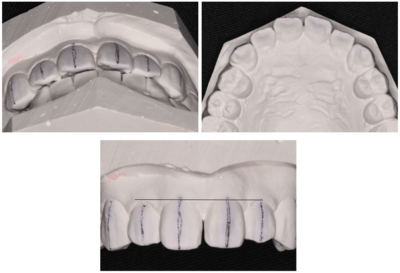

マルモ診断

・左上1番の唇側転位による正中離開

・左上2番の位置が上方へややあともどり

・OJはあるが、下顎との被蓋関係は問題なさそう

・左下12番間も若干スペースがあるが、そこは気にならないとのことで治療はしない

ブラケット・ワイヤー装着

まずはブラケットを装着。審美的になるべく阻害がないように、透明なブラケットを使用した。

2週間後

ワイヤーはまだたわみがあるが正中はやや閉鎖してきた。

更に2週間後

正中はほぼ閉じた。ワイヤーのたわみも無くなってきた。

もうすこし左上2が頬側に出てほしい。

完成。

保定もかねてワイヤー(1622SS)変更。

1ヶ月後

ブラケット除去。

同時に予定していた保定装置のマウスピース用の印象をおこなった。

正中離開、左上2の位置、被蓋関係、全ての改善をすることができた。しかもたったの2ヶ月!

翌日、ハードタイプ1ミリのマウスピースを保定装置として使用させるために作成しお渡した。